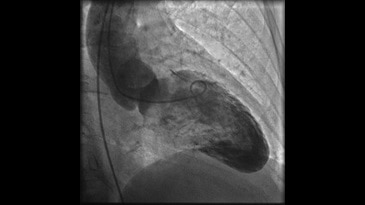

- Innova 3D — получение трехмерных изображений в операционной. Программное обеспечение трехмерной ангиографии Innova 3D — это режим получения трехмерных изображений из ротационной ангиографии, предоставляющий точную сосудистую визуализацию, непосредственно у операционного стола. Приложение позволяет получить трехмерную реконструкцию с высоким пространственным разрешением путем измерения спектра плотностей окружающих тканей;

- Subtracted 3D — визуализация только области интереса. Автоматическое вычитание и отображение трехмерной модели для четкой визуализации интересуемого анатомического объекта. Позволяет быстро визуализировать сосуды без необходимости вырезания окружающих костных структур, ткани и имплантированных устройств. Прозрачность имплантируемых устройств и кальцифицированных бляшек может настраиваться для безупречной визуализации анатомических особенностей сосудов;